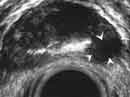

Эндовезикальное сканирование позволяет выявить распространение опухоли на интрамуральный отдел мочеточника (Рис.7) и предстательную железу (стадия Т4). Однако следует отметить, что при инвазии опухоли в предстательную железу более информативным является трансректальное сканирование. Что касается распространения опухоли на другие органы и ткани (брюшина, кости таза, тонкий кишечник и прямая кишка), то возможности эндовезикального исследования здесь ограничены. В подобных случаях значительную помощь в диагностике оказывает компьютерная томография. То же самое можно сказать и о диагностике метастатического поражения регионарных лимфатических узлов.

Рис. 7. Цистэндосонограмма. Рак мочевого пузыря с врастанием в интрамуральный отдел мочеточника (стрелкой указан расширенный мочеточник).